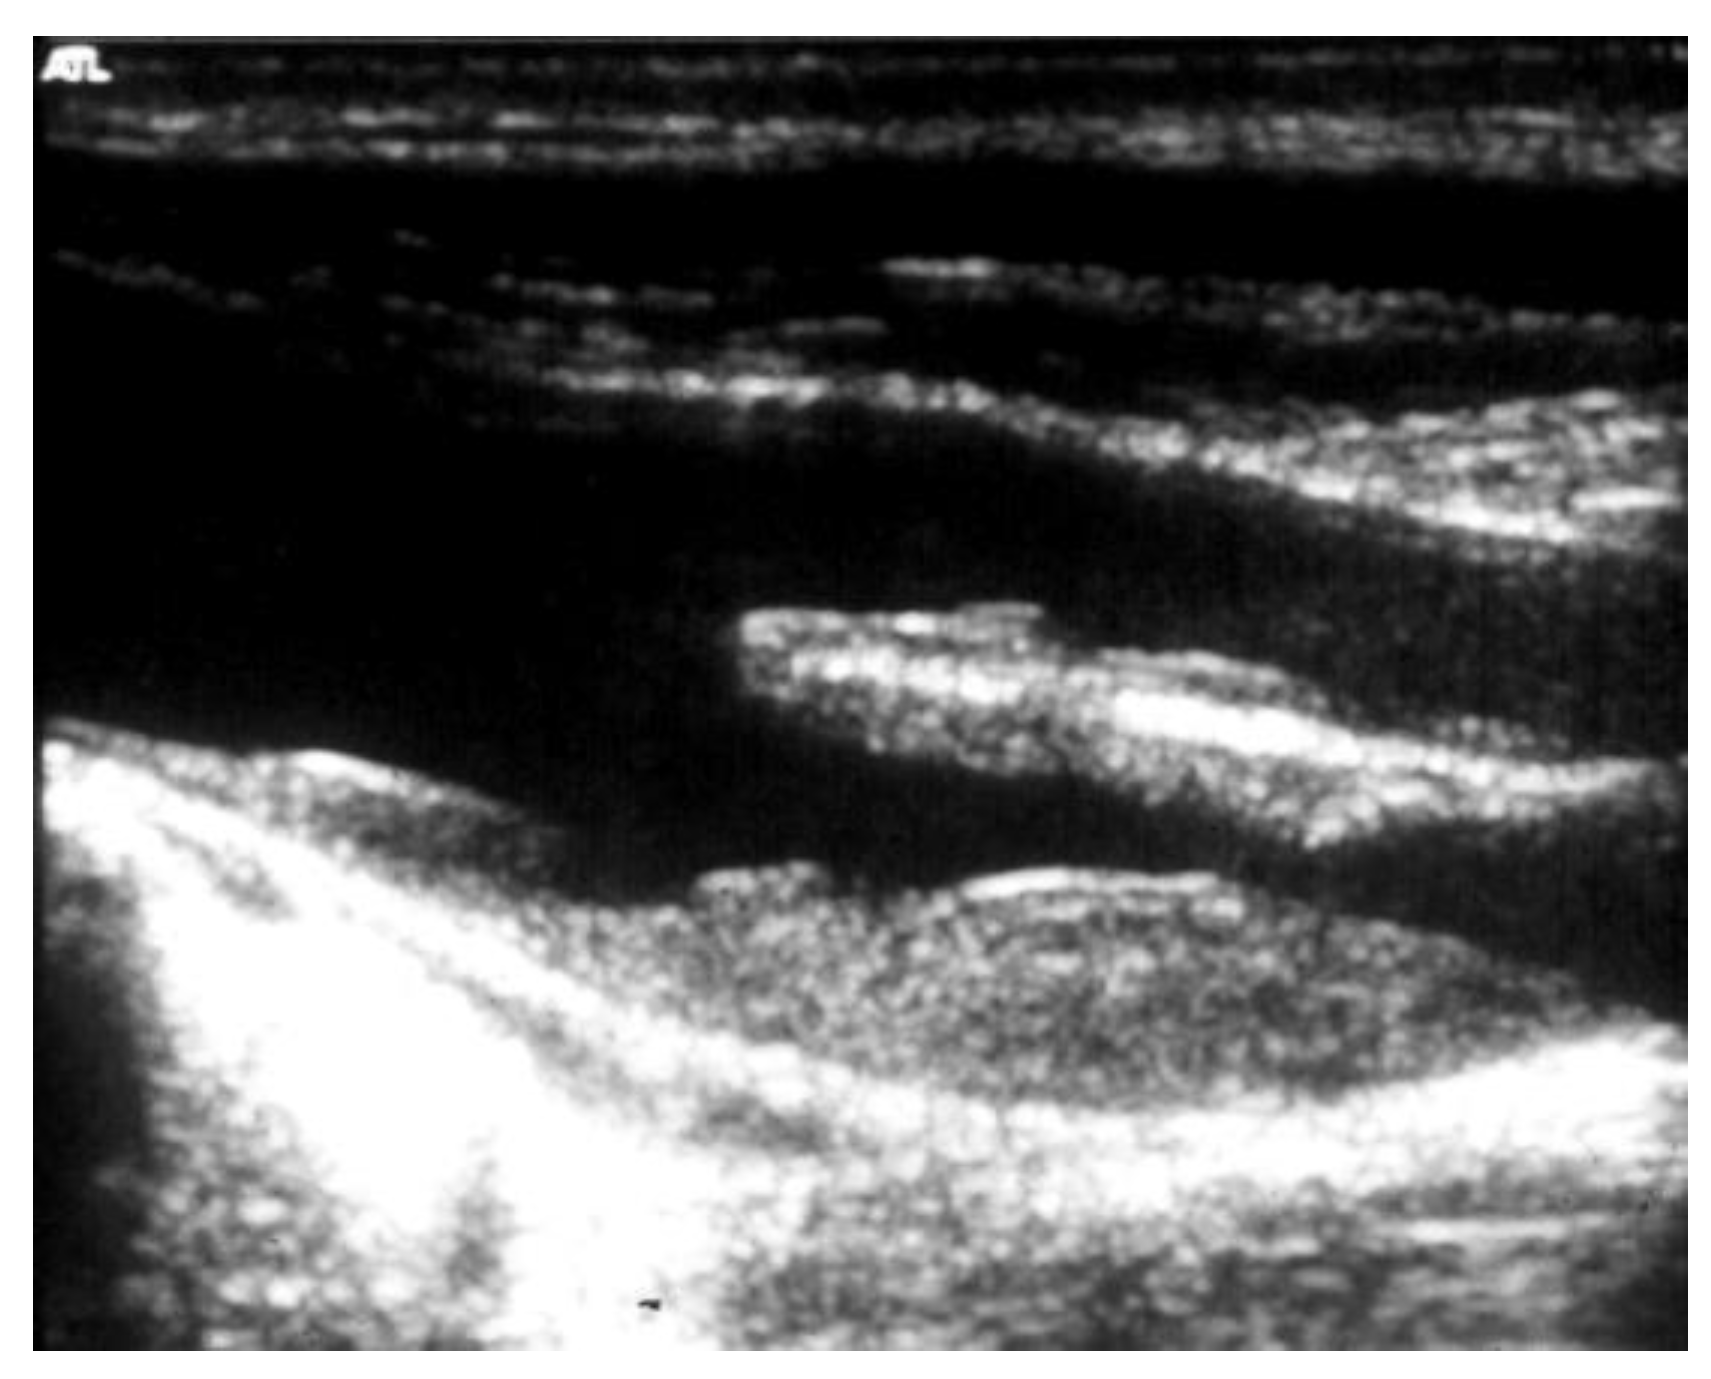

Then, the eventual clinical suspect of an AAA needs to be confirmed or excluded by a first-level investigation, such as a duplex scan, which has a very high specificity (almost 100%) and sensitivity (95%) to detect an AAA (Figure 3) [24].

Figure 3.

Duplex scan of the abdominal aorta can easily confirm the clinical suspect of abdominal aortic aneurysm. Short axis (left) and long axis (right) view.